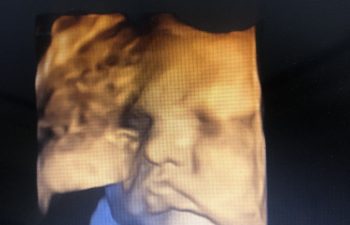

Welcome to Our World, Jillian Jamie

Last Thursday morning, our lucky little 7/11 baby girl made her grand entrance at 9:24 a.m. here in Madison, Alabama following a successful induction. (I hope to share the birth story soon, if you’re interested.) She weighed in at 7lb 14oz and is 20″ long. She has a head full of long, dark hair (our first baby with not only… Keep Reading